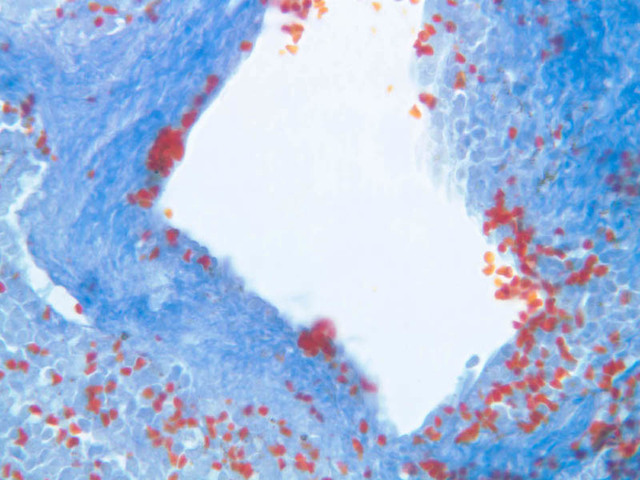

The remainder of the cellular mass in the spleen is red pulp (A-38 [10x, 20x, 40x]), made up of red and white cells of the blood enmeshed in the reticular tissue of splenic cords and present in the splenic sinuses. After passing through the PALS, the trabecular arteries branch to form smaller arterial vessels known as penicillar arterioles which narrow, forming arterial capillaries that empty into the cords of the red pulp (open circulation) or into the venous sinuses (closed circulation). In the splenic sinuses the cells of the blood are exposed to red pulp macrophages. The splenic sinuses eventually become confluent to form veins that enter the trabeculae and gradually merge meeting in the hilus to form splenic veins.

Examine the composition of the red pulp tissue. The three dimensional structure of the red pulp is analogous to Swiss cheese with the holes being the venous sinuses and the cheese being the parenchyma (i.e. splenic cords). On slide A-36 which is stained with Mallory's aniline blue locate examples of the splenic sinuses ([2.5x, 10x, 20x, 40x-labeled] [10x, 20x, 40x]). The walls of the splenic sinuses consist of adjoining specialized endothelial cells whose nuclei in many cases stand out from the wall in a bead-like fashion. The basement membrane of the epithelial cells stains blue revealing the sinuses quite nicely. Usually the sinus lumen is filled with red cells and leukocytes. The skeletal framework of the cords is provided by a network of reticular fibers. As above, the reticular cells are best seen using a reticular fiber stain (slide A-37 [2.5x, 10x, 20x, 40x-labeled]). Look for the large pale nuclei of reticular cells that have darkly stained reticular fibers. Fibers run irregularly in the cords, but clearly outline the sinuses around which they are wrapped. Notice on this same slide that there is much less reticular tissue in the white pulp than the red. The splenic cords occur around the sinuses and are distinguished by the presence of disintegrating red blood cells undergoing phagocytosis.